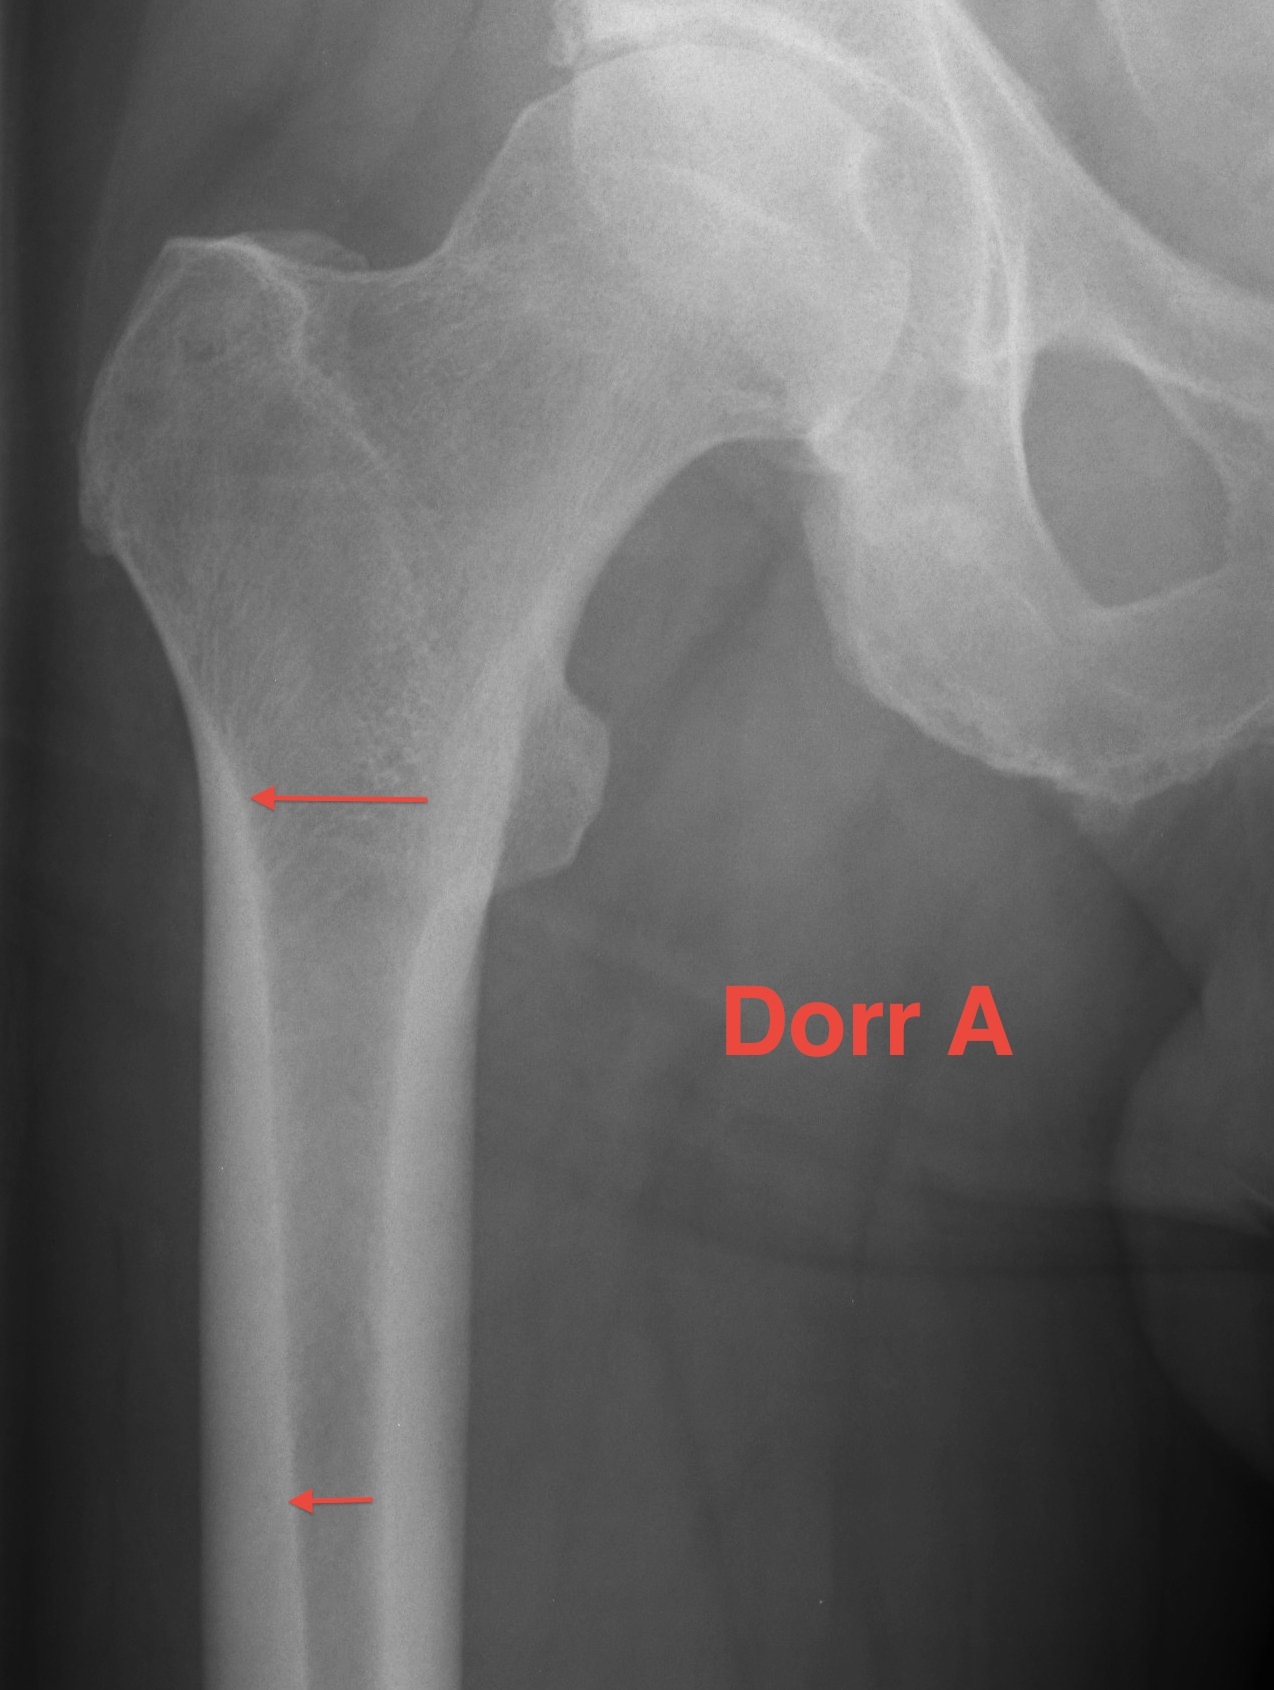

Dorr Classification of Proximal Femoral Geometry

Technique

- measure intra-medullary canal at lesser trochanter & 10cm below

- diameter 10 cm distal divided by inner diameter at midportion of lesser trochanter

- must be <75% for uncemented prosthesis

| Type A / Champagne Flute | Type B | Type C / Normal |

|---|---|---|

| Ratio < 0.5 | Ratio 0.5 - 0.75 | Ratio > 0.75 |

| Thick cortices | Wide canal diameter | |

| Young males | Elderly females | |

| Small diaphysis and thick cortex risks fracture | Cemented stem |